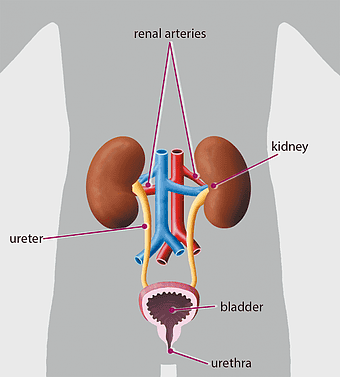

urinary system anatomy, kidney function illustration, ureter diagram, bladder infection symptoms, renal system health, excretory function chart, genitourinary medical diagram -

1200x1200px

human excretory system diagram, kidney and bladder anatomy, urinary system function, renal arteries and ureters, human body organ systems, medical illustration of kidneys, biological diagram of excretory organs -

680x654px